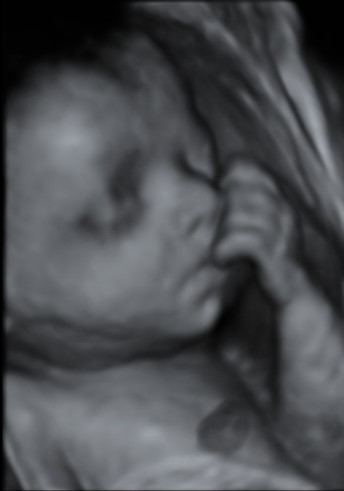

Black And White 3d Ultrasound Pictures

3d 4d 5d Ultrasound In Midland Tx Here Is Baby